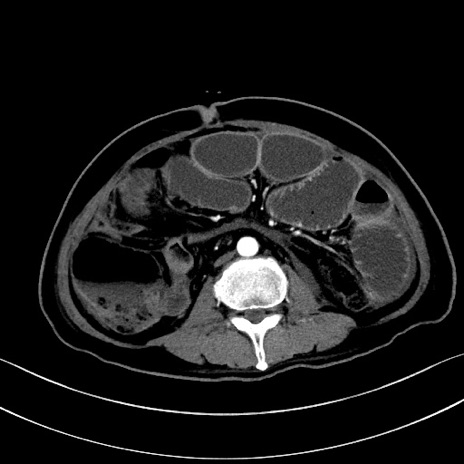

冠状断像

【症例】60歳代男性

【主訴】嘔吐

【現病歴】胃癌にて胃全摘後。食思不振が悪化し、夜中に嘔吐することがある。

【既往歴】胃癌、胃全摘、脾摘、胆摘後

【データ】WBC 5900、CRP 10.56